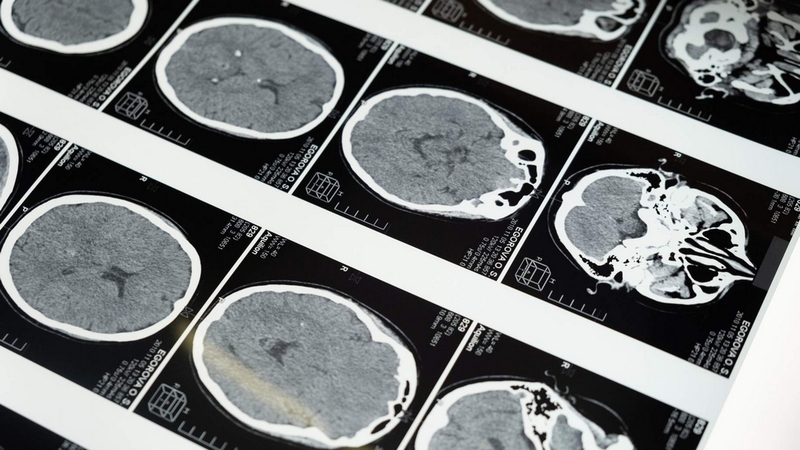

U sọ hầu (Craniopharyngioma) là một khối u lành tính rất hiếm gặp ở não, hay khối u nằm sát xương sọ này còn được gọi là khối u túi Rathke. Theo số liệu thống kê, tỷ lệ người bệnh xuất hiện khối u ở gần vị trí xương sọ là khá ít, chỉ chiếm khoảng 2 - 4% tổng số bệnh nhân bị u não. Các khối u sọ thường gặp nhiều ở trẻ em (với tỷ lệ chiếm khoảng 50%) và không có sự phân biệt về giới tính (tỷ lệ mắc bệnh giữa trai và gái là tương đương nhau). Đặc biệt, phần lớn bệnh thường xuất hiện ở nhóm trẻ em từ 5 - 10 tuổi.

Mặc dù là khối u lành tính, nhưng vì u sọ hầu xuất hiện ở vị trí gần với cuống của tuyến yên, là nơi sản xuất ra nhiều loại hormone trong cơ thể nên về lâu dài, khối u này có thể ảnh hưởng đến chức năng của tuyến yên và các cơ quan lân cận. Ngoài ra, vì nhóm đối tượng thường gặp nhất là trẻ em, cho nên bố mẹ là những người cần hết sức quan tâm, theo dõi bé để có thể phát hiện và cho bé điều trị sớm nhất có thể.